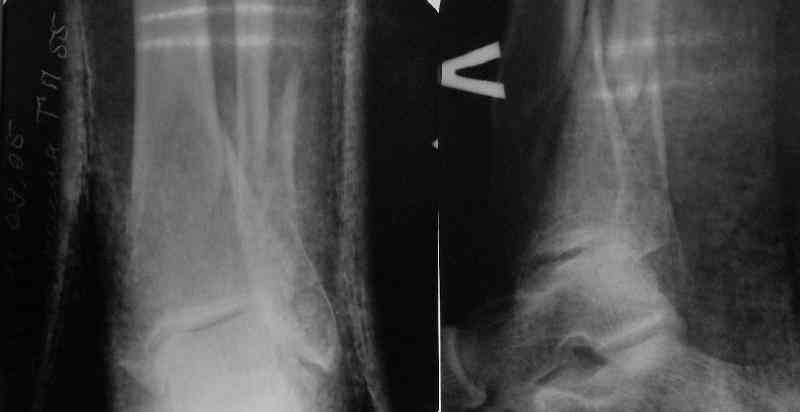

Направили к нам пациентку 35 лет с переломом дистального отдела костей голени.

У нас сделали снимок сзахватом обоих суставов - еще и проксимальный метафиз сломан. Чем бы у вас фиксировали такой перелом? Как его правильно закодировать по классификации АО?

На ренгенограмме эпиметафизарный перелом вроде

внутрисуставной, если это доказать через КТ, тогда

перелом будеть считаться tibial plateau, лечение будет отличаться от лечения сегментарных переломов.